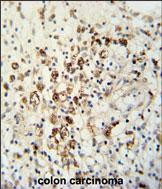

| IHC | 1/100-1/500 | Human,Mouse,Rat |